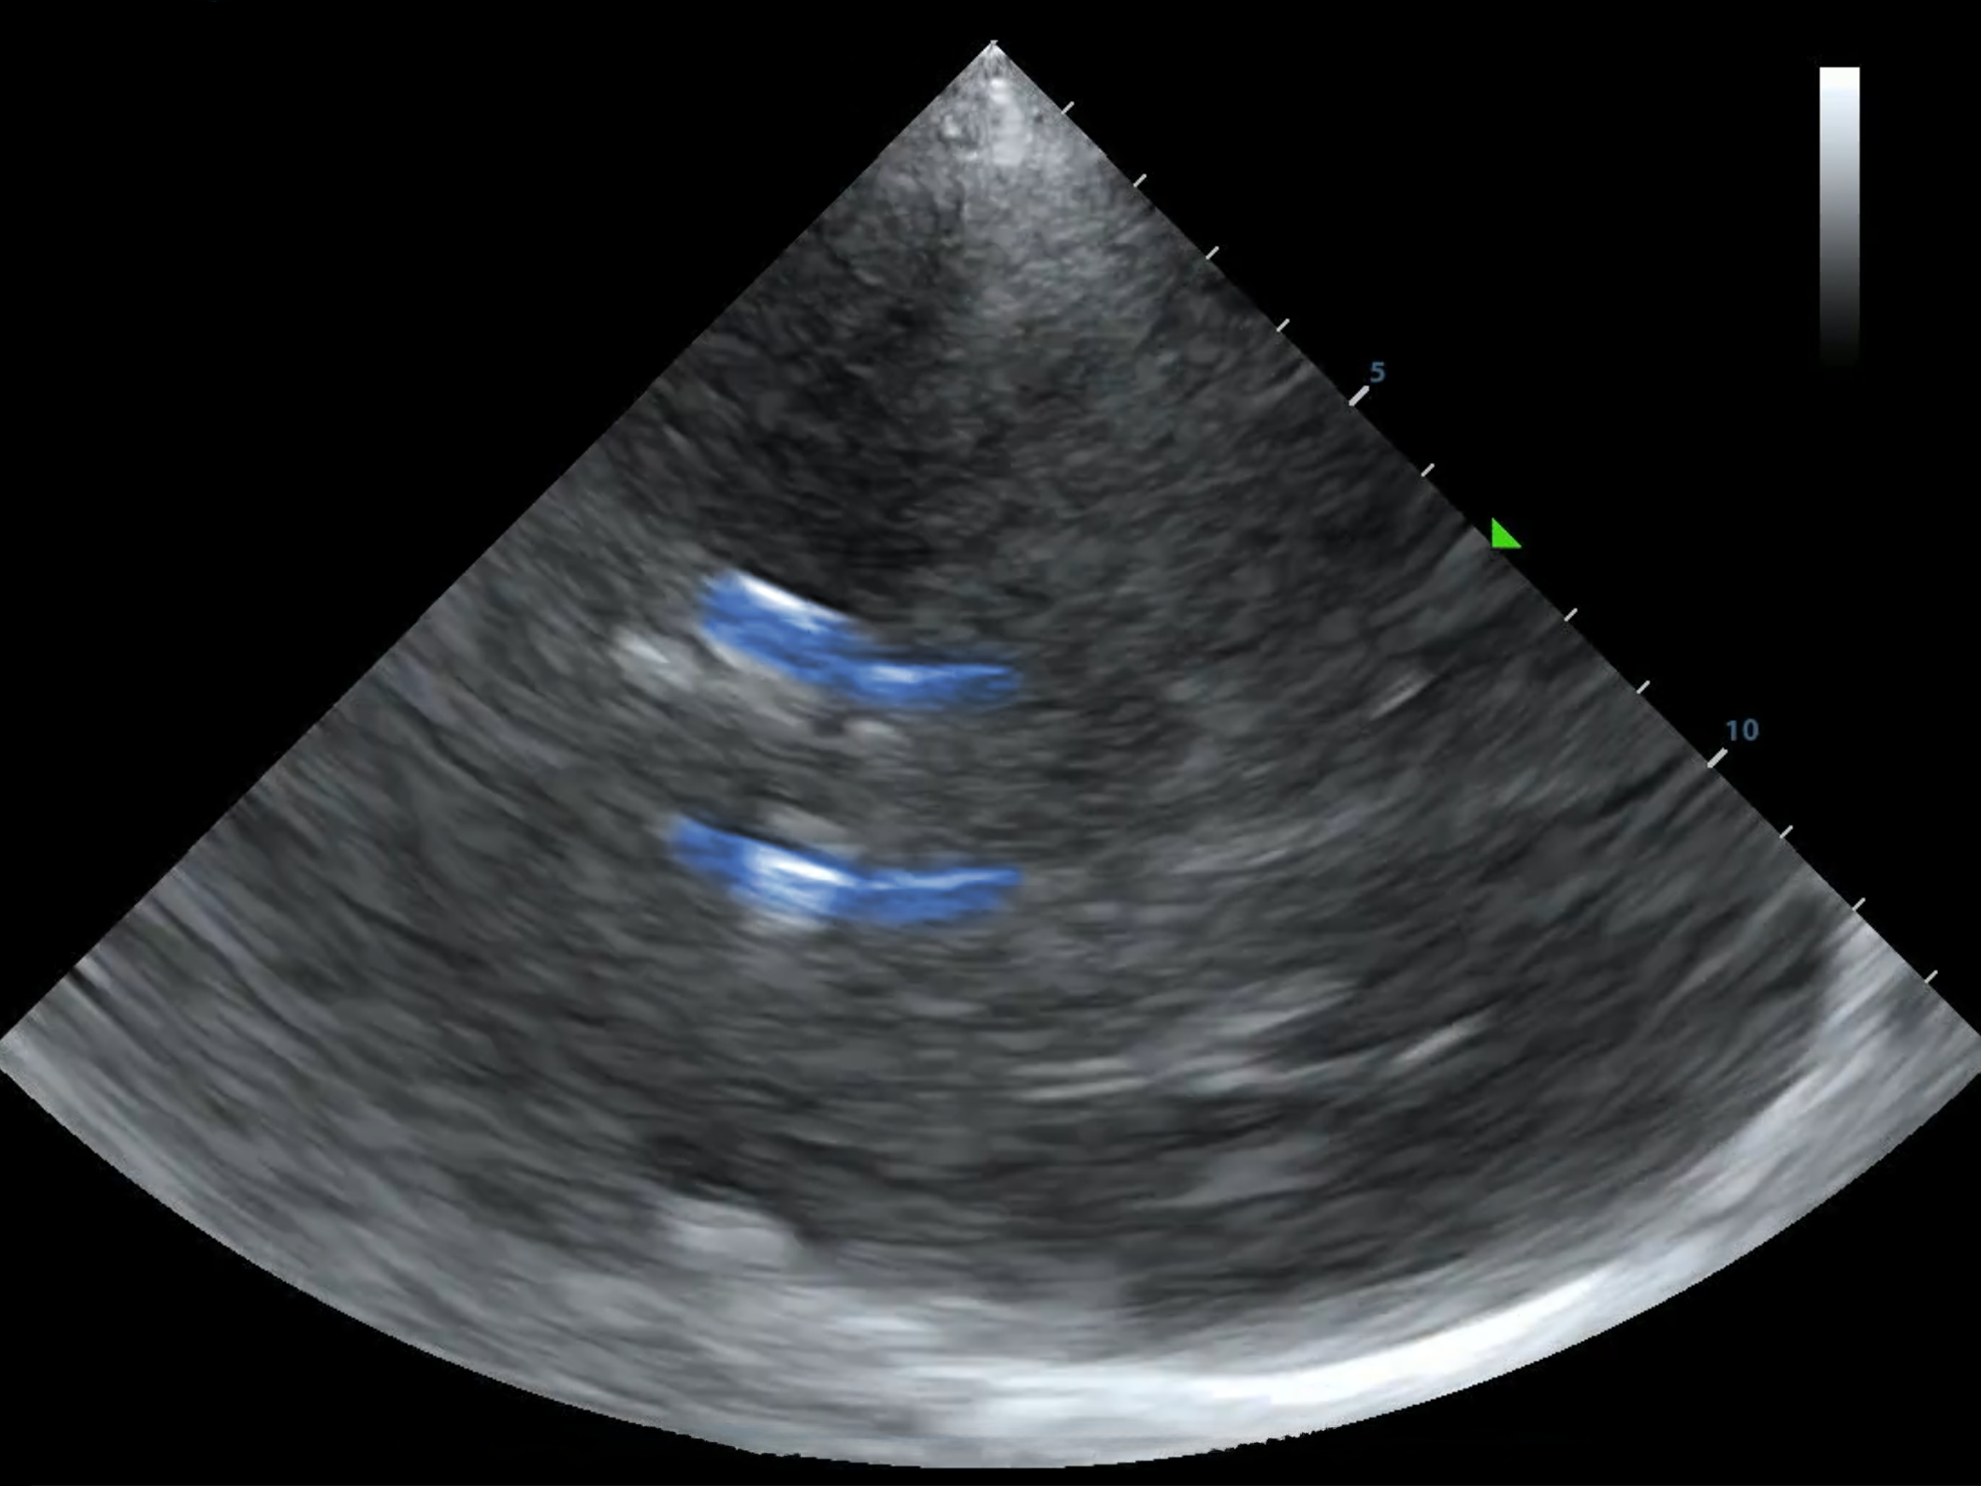

B-Mode Anatomy